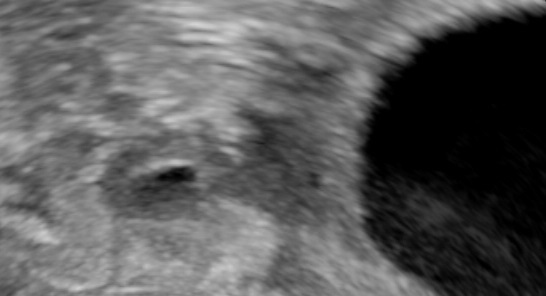

Tiny tubal ectopic.